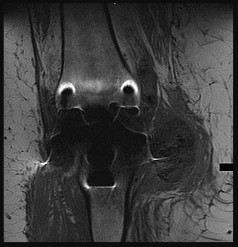

Figures 6a through 6d are the radiographs and T1-weighted sagittal and fat-saturated axial MR images of an otherwise healthy 56-year-old man who has anterior knee pain and intermittent swelling after sustaining a noncontact twisting injury. Low-power and high-power hematoxylin and eosin stained histologic specimens are shown in Figures 6e and 6f. Based on the history, radiographs, CT scan, MR imaging, and histologic findings, what is the most likely diagnosis?

The lesion in the posterior intercondylar knee notch is a benign synovial hemangioma. Intralesional calcifications, classically associated with hemangiomas, are frequently not identified on plain radiographs. The MR imaging reveals a hypervascular lesion with multiple filling defects, with hyperintensity on T2-weighted images and low-to-intermediate signal intensity on T1-weighted images. Histologically, vascular lakes within fine capillaries with a synovium on the surface of the lesion are characteristic of this condition. Many patients with synovial hemangioma have pain, swelling, stiffness, or mechanical symptoms. The correlation of symptoms with the hemangioma for this patient is unclear because there was recent trauma and a concurrent meniscus tear. Simultaneous treatment of both potential sources of pain is typically recommended. As with PVNS, the disease can be localized or diffuse. Surgical excision, either open or arthroscopic, is the recommended treatment. PVNS is the most common intra-articular tumor, but hypointensity in either the diffuse or localized type is characteristic in both T1- and T2-weighted images. Synovial sarcoma, although often found close to a joint, is not characteristically found within a joint.